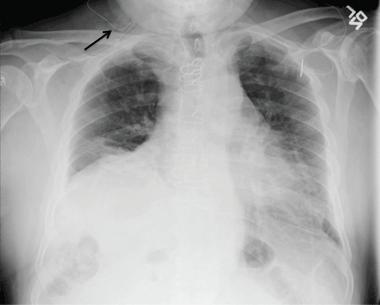

72-year-old man

๐Ÿ‘‰underwent arthroscopic repair of the rt shoulder

For postoperative pain, a supraclavicular catheter was placed for brachial plexus block

The next day๐Ÿ‘‰ right-sided chest pain and mild shortness of breath

Diagnosis?

A 72-year-old man underwent elective ambulatory arthroscopic repair of the right shoulder rotator cuff.

To manage postoperative pain, a supraclavicular catheter was placed for brachial plexus block

๐Ÿ‘‰he was sent home with a ropivacaine infusion pump.

The next day, he presented to the emergency department with right-sided chest pain and dysnea

Phrenic nerve paralysis induced by brachial plexus block